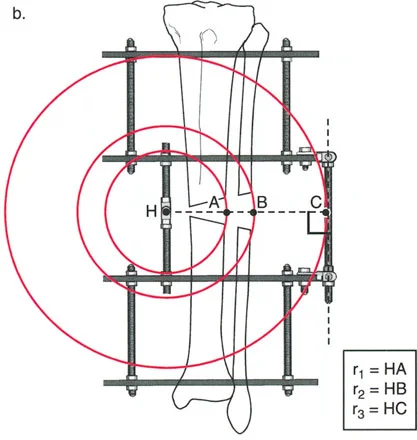

لحساب المعدل الصحيح للشد عند المفصلة، نستخدم قاعدة المثلثات المتشابهة، والتي تعتمد أساسًا على القاعدة الهندسية للدوائر متحدة